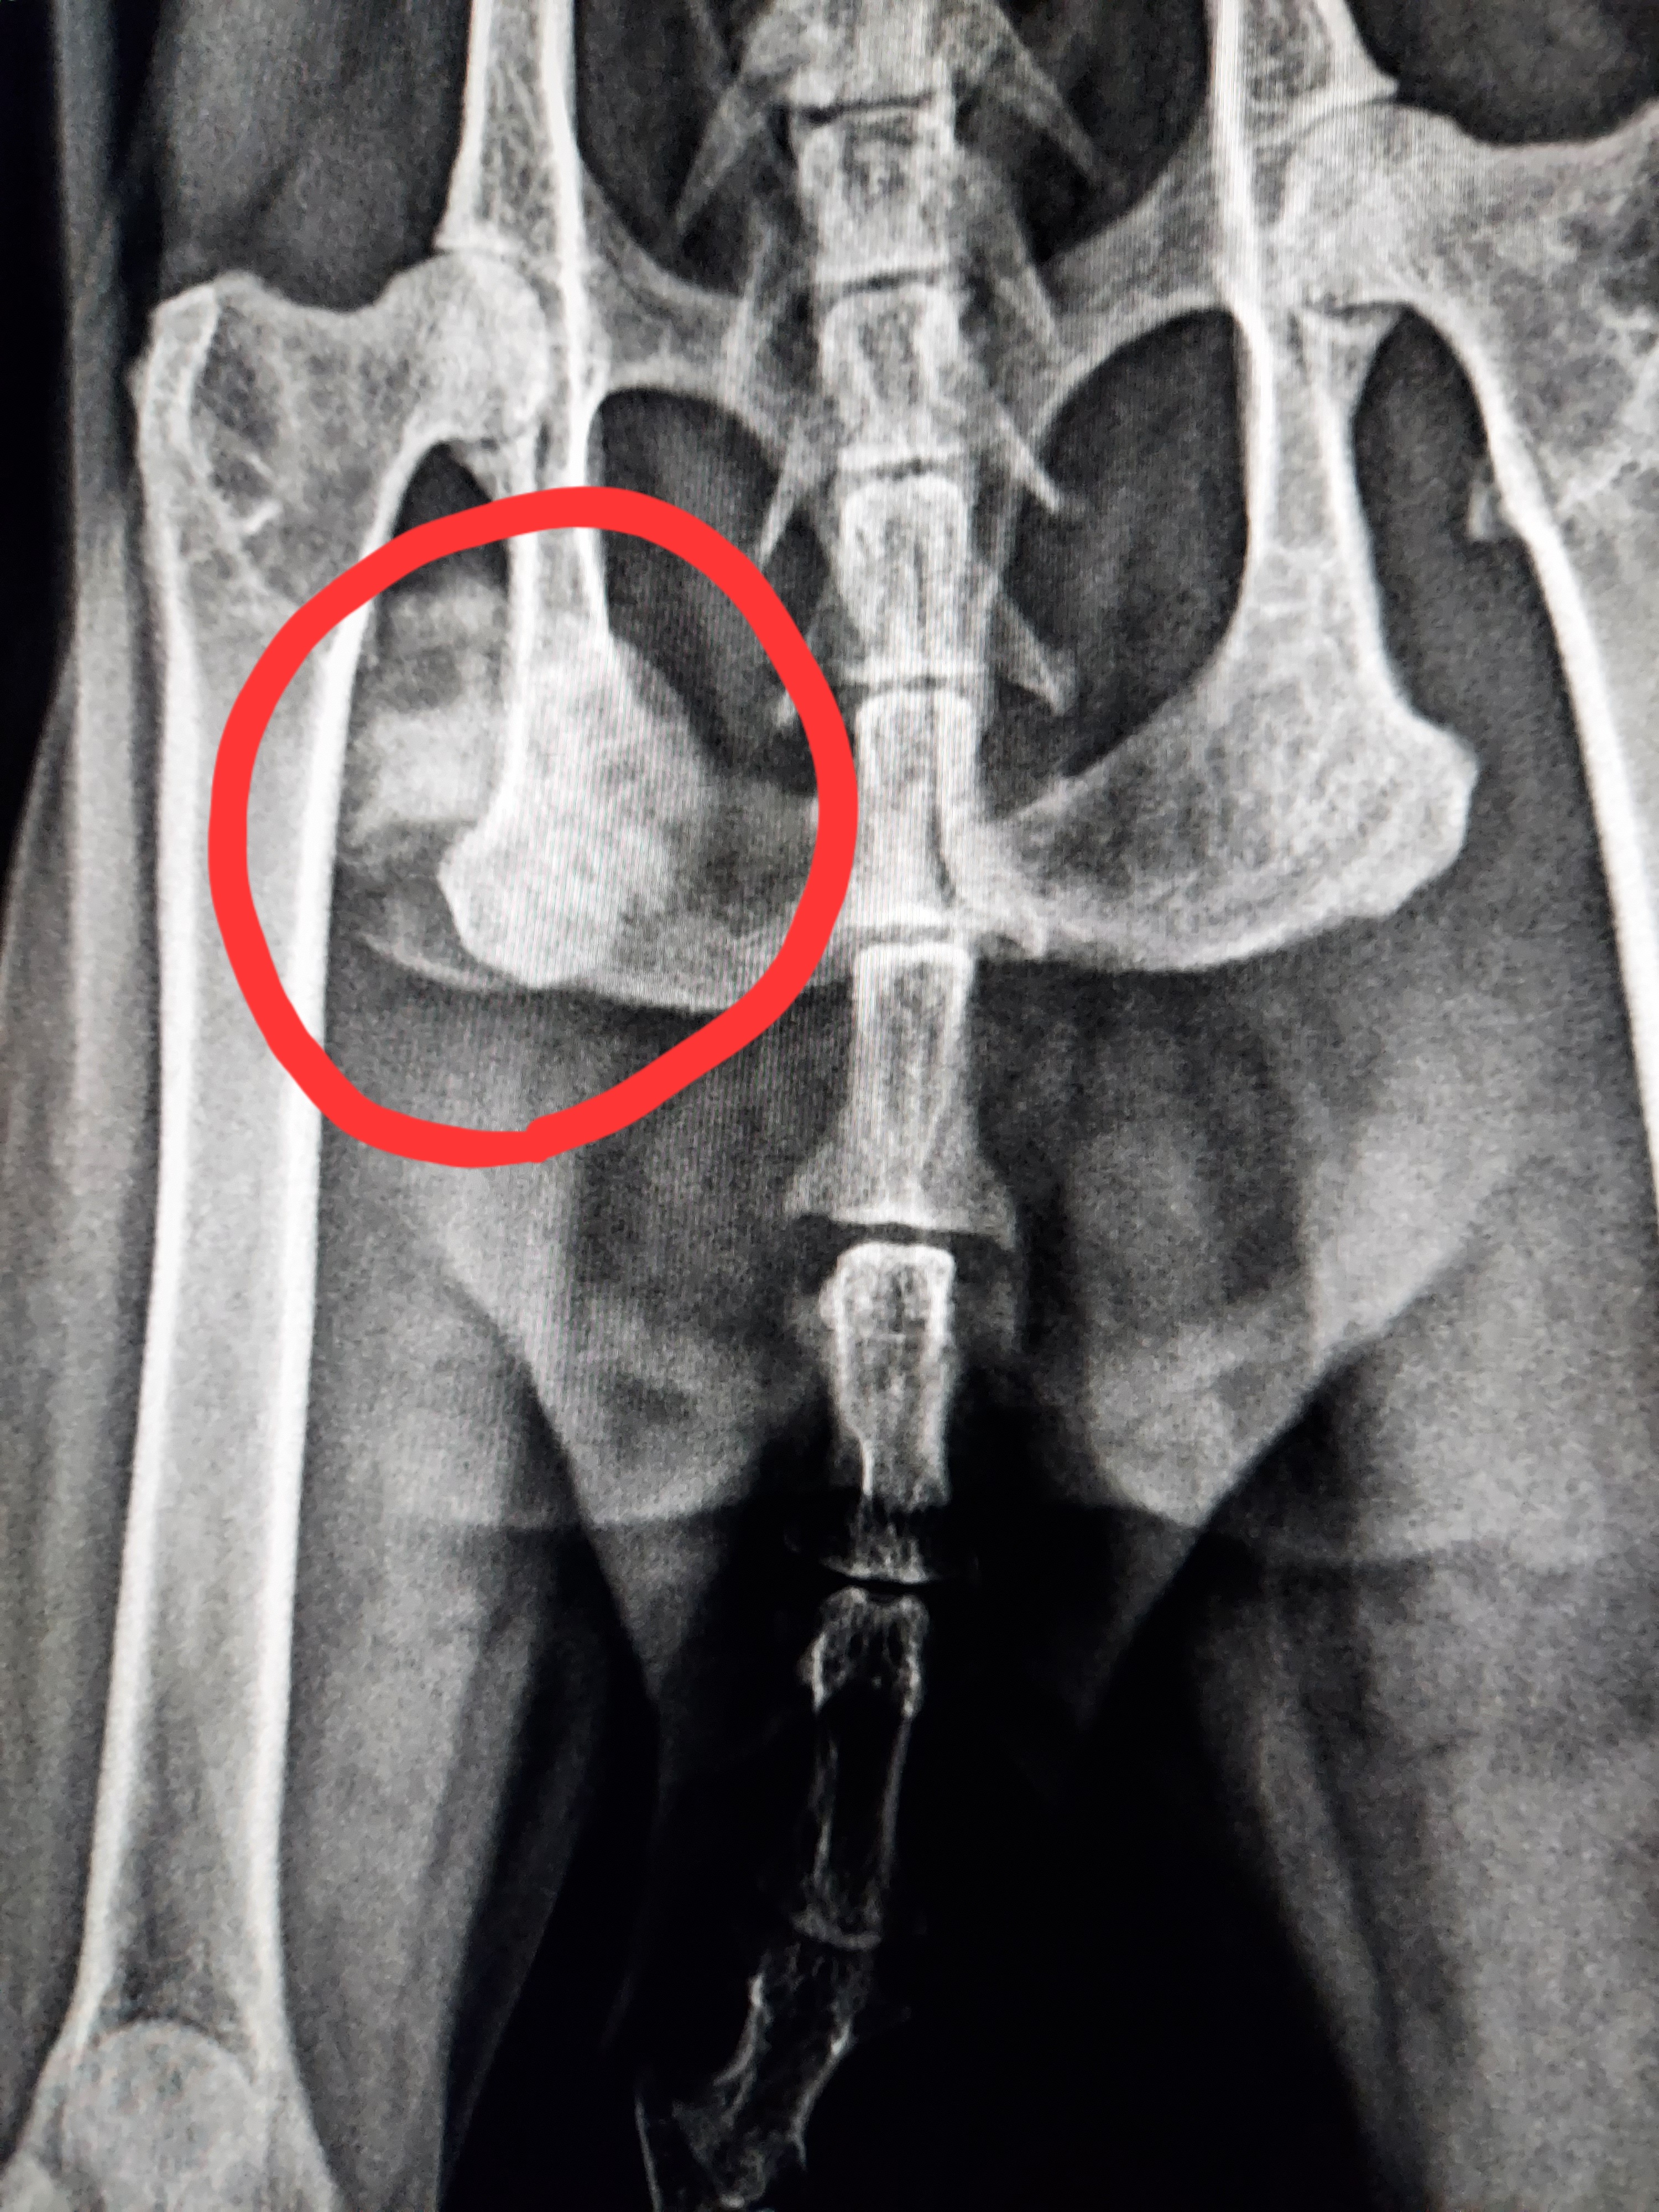

肺のモヤモヤしたものは見あたらなくなったようですが、右の骨盤に腫瘍と思われるものがありました。

おそらくこれが元のガンで、あちこち転移しているようです。